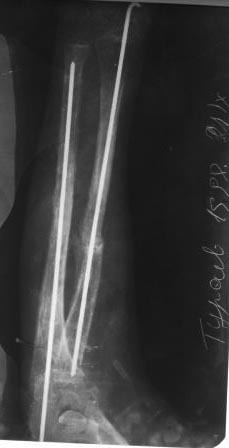

Уважаемые коллеги. Обратился мальчик 1998г.р. с жалобами на деформации предплечья. Со слов матери 2008г оперирован мною по поводу перелома обеих костей предплечья. и/м остеосинтез спицами ( с 2010года перешли на пластины-DCP,LCP).через 2 месяца после заживления спицы удалены, я сам не помню. И через 7 лет явились с претензиями что со слов больших докторов из центра неправильно оперирован и якобы спицы удалены раньше срока и поэтому развился такая деформация. Я не понял, почему развилась такая атрофия и дефект локтевой кости, ведь по представленным снимкам п/о и через 2 месяца все было нормально... или родители чего-то скрывают..Функция локтевого и луче-запястного суставов сохранены, имеется небольшое ограничения супинации и пронации. Я обещал родителям, что выложу на форуме, и совместно с опытными специалистами подумаем.В плане корригирующая остеотомия лучевой кости, резекция концов ложного сустава локтевой кости . аутотграфт из половины окружности малоберцовой кости достаточной длины, остеосинтез методом Илизарова. Уважаемые коллеги , жду и надеюсь на Ваши рекомендации.. С уважением Абдурашид.

Уважаемый Alexander, спасибо. но больной хочет служит в армии, поэтому и требует исправит деформацию.

Уважаемый Александр, у нас БИОС делается на бедро,голени и плече, пока гвоздей для предплечья не поступали, поэтому этот метод отпадает, и/м спицы у детей мы удаляем и через 1. и 1,5 месяца и никогда такого за 39 лет работы я не видел!.а в данном случае по Р-снимкам локтевая кость через 2 месяца полностью срослась!а потом что случилось локтевой костью не понимаю. мы же даже у взрослых после консервативного лечения наружную фиксацию снимаем через 2 месяца,.

Добрый день, уважаемые коллеги. По моему вы недостаточно серьезно оцениваете имеющуюся ситуацию. При первом взгляде на рентгенограммы возникает только одна аналогия - латентный ложный сустав костей голени. Тот же дефект малоберцововй кости, та же дугообразная деформация большеберцовой кости. Можно лишь гадать о том, что послужило пусковым механизмом развития такой деформации костей предплечья, но сейчас вы имеете дело с явным нейротрофическим нарушением на данном сегменте.

И вам придется давать ответы на несколько вопросов. Возможно ли без укорочения исправить угловую деформацию лучевой кости. Как надежно заместить дефект локтевой кости. Здесь уже нельзя говорить о ложном суставе, поскольку после исправления деформации предплечья диастаз между фрагментами увеличится. Предлагаемый метод пластики вызывает большие сомнения, поскольку имеются явные трофические нарушения дистального фрагмента локтевой кости. Наиболее надежна в этом случае микрохирургическая аутотрансплантация малоберцовой кости.

Уважаемые доктора, рассуждать сейчас о причиных деформации предплечья и формирования дефекта локтевой кости достаточно сложно. Вероятно сама травма и последующие вмешательства привели к выраженному нарушению васкуляризации диафиза локтевой кости. Атрофия мышц предплечья связана с локальными нейро-трофическими изменениями на уровне проксимальной/3 предплечья.Для исправления подобных деформаций в нашем институте травматологии применяются корригирующие остеотомии лучевой кости с одновременной пластикой дефекта локтевой кости сегментом малоберцовой кости на микроанастомозах, с обязательной ревизией сосудисто-нервных пучков.